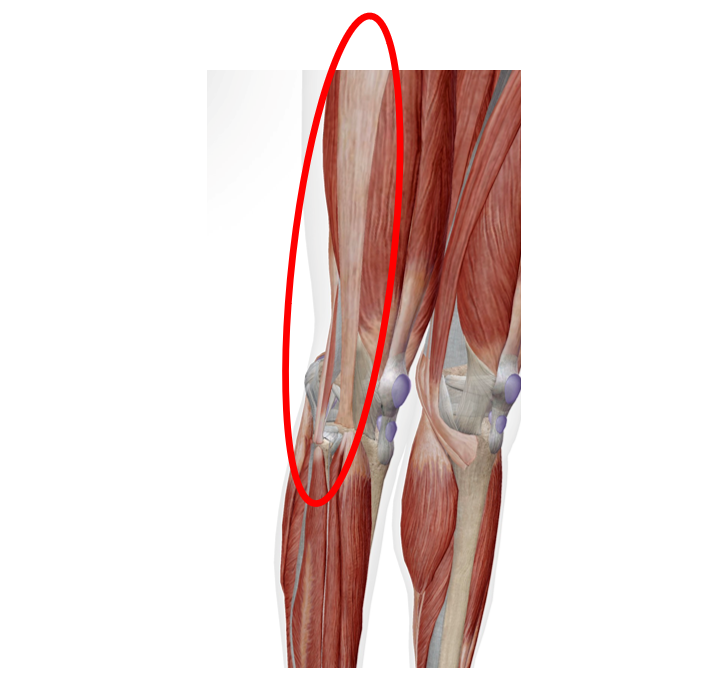

赤い丸のあたりが痛むでしょうか?

今回は「膝の外側の痛み」について解説します!

腸脛靭帯(上の図の位置にあります)炎の症状としては、運動後に膝の外側に痛みが出ます。痛みが出る場所は、膝の外側の出っ張っている部分です。また久しぶりにランニングをしたり、運動をすると痛いことがあります。